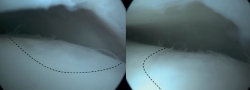

La perforación retrógrada es una técnica no transarticular, que utiliza la fluoroscopia para la visualización del astrágalo, lo que permite desbridar y perforar el quiste subcartilaginoso. La perforación retrógrada puede considerarse una intervención quirúrgica para las OLT quísticas con una capa de cartílago articular intacta(22). La perforación retrógrada permite penetrar en la zona esclerótica necrótica para estimular la médula ósea sin dañar la superficie intacta del cartílago(37). Al igual que la EMO, la perforación retrógrada provoca la interrupción de los vasos sanguíneos intraóseos y, por tanto, favorece el relleno óseo subarticular del quiste. Tras exponer el astrágalo utilizando los portales anteromedial y anterolateral, se colocará una aguja de Kirschner bajo control fluoroscópico, transtalar desde el cuello astragalino opuesto hacia la zona subcondral esclerótica(37).